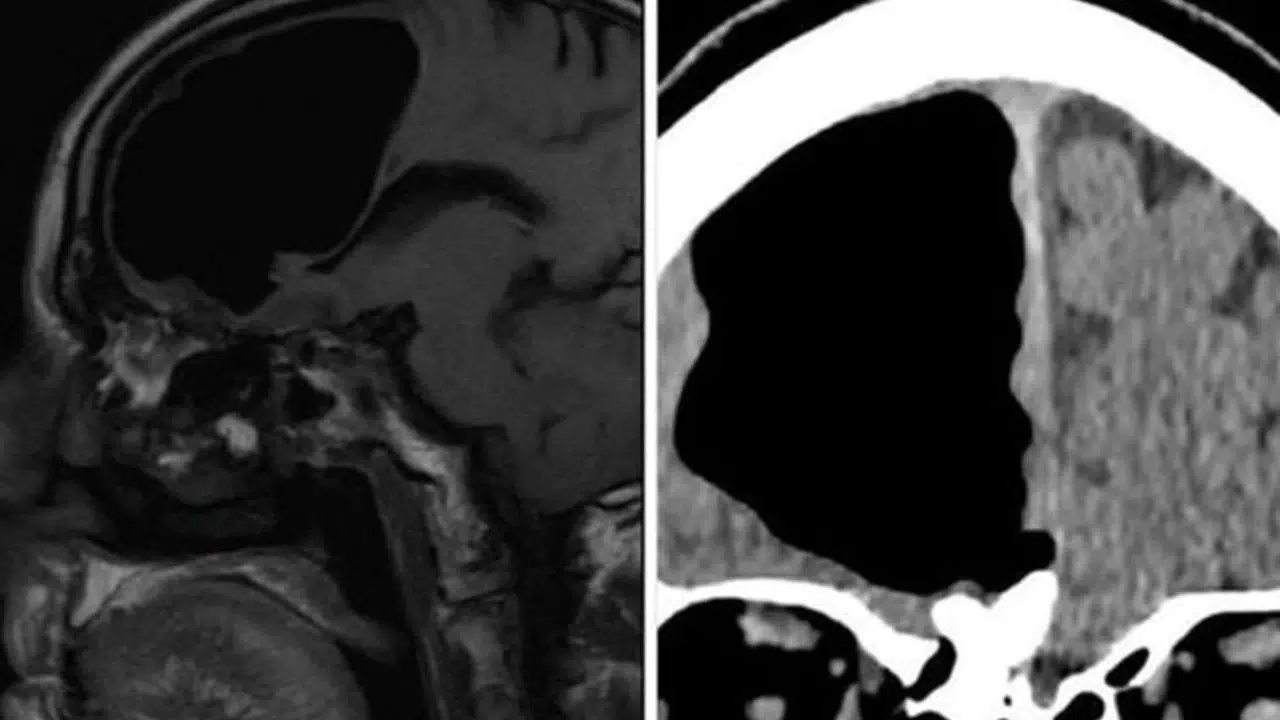

MR ve CT sonuçlarına bakan doktorlar, adamın beyninin ön sağ lobunda yaklaşık 9 santimetrelik bir boşluk vardı. Adamın beynindeki bu boşluğun yerine hava olduğunu söyleyen yetkililer, “Genellikle bir beyin ameliyatı sonrasında hava basıncının değişmesi dolayısıyla bu tür sıkıntılar yaşanabilir” dedi. Washington Post’a konuşan doktorlarda Finlay Brown, “Araştırmamı yaparken, bu durumun bir benzerine rastlamadım. Bu rahatsızlığa sebep olan şeyin burnunu çekmek, hapşırmak ve öksürmek olduğu biliniyor. Bunlar her yapıldığında insanın kafasına belli miktarda hava depolanır” dedi.